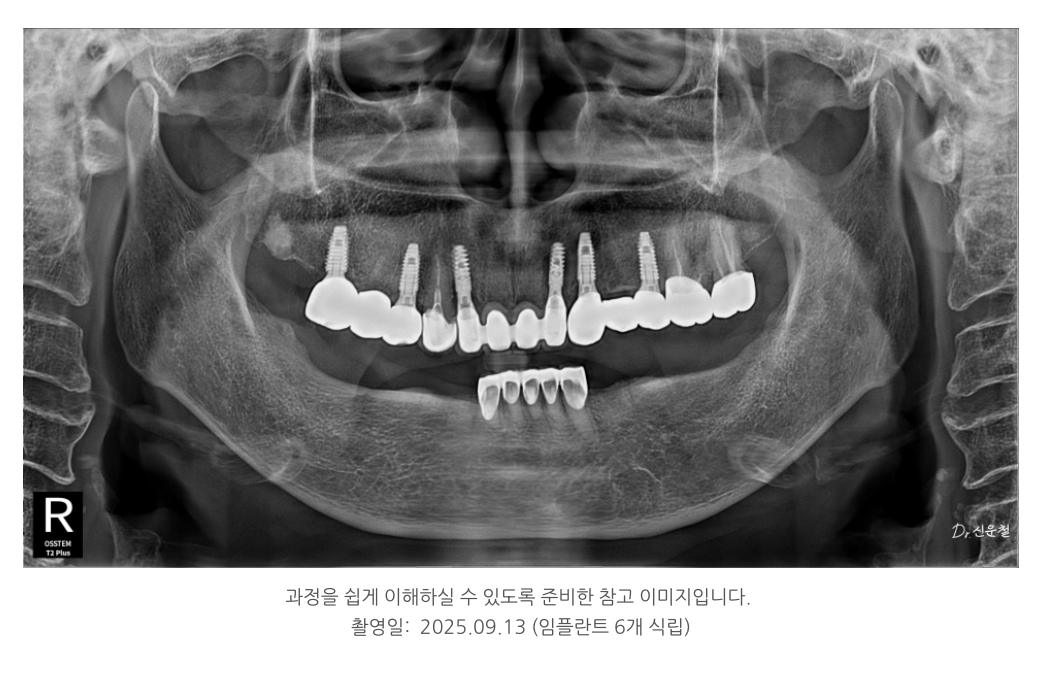

윗니: 임플란트 6개 (보험 2개 포함)

아랫니: 부분틀니 + 크라운 보강

???? 비용 부담은 절반 이상 줄이면서

식사, 발음, 외적인 만족도 모두 개선되었습니다.